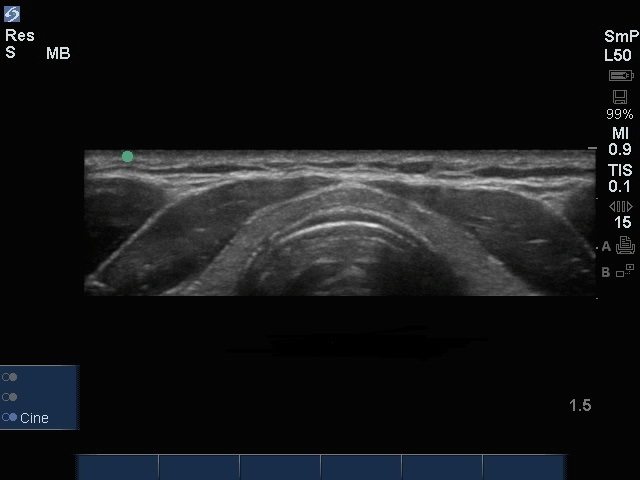

甲状腺峡部画像